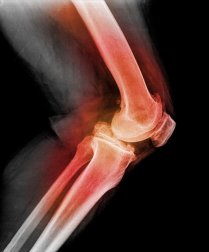

Attraverso la radiografia, la risonanza magnetica (RM) o la tomografia computerizzata (TC) è possibile ottenere immagini della lussazione o di altre lesioni del ginocchio. I sintomi di una lussazione della rotula sono invece i seguenti.